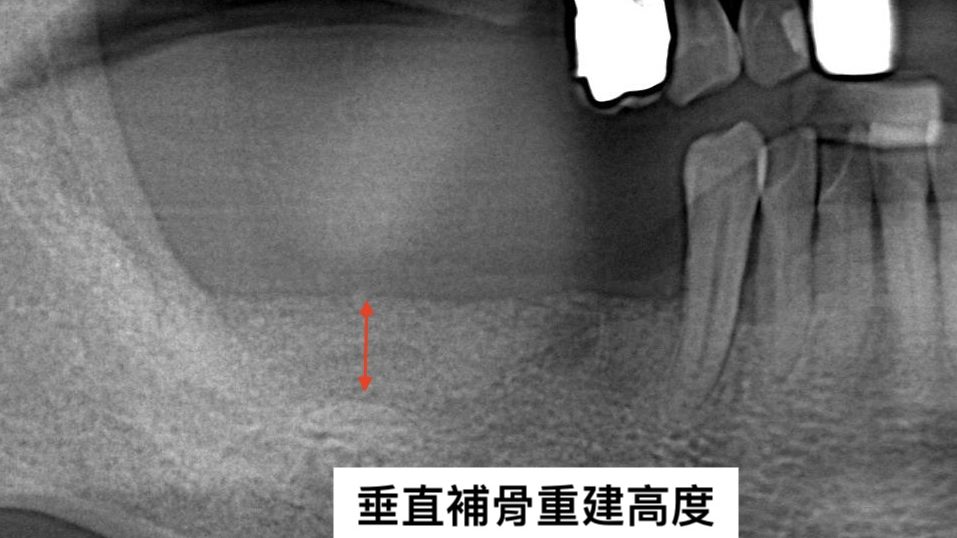

透過3D電腦斷層與口腔掃描,先全面檢查牙齒與骨頭狀況,並建立3D模型。醫師會以此確認所需補骨範圍、預先模擬手術效果,並決定適合的手術方式。

由專科醫師親自操作,以骨粉重建缺損的部位,視狀況使用鈦支架加強結構,再蓋上再生膜隔離牙齦組織,引導齒槽骨與牙周組織再生。